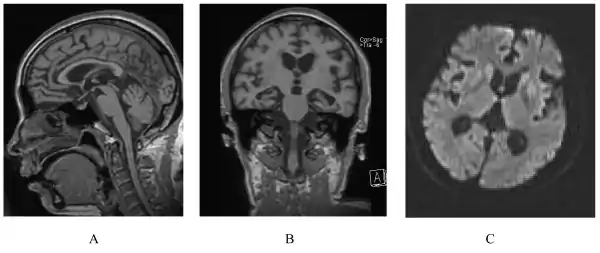

| A person with inherited prion disease has cerebellar atrophy. This is highly typical of GSS. | |